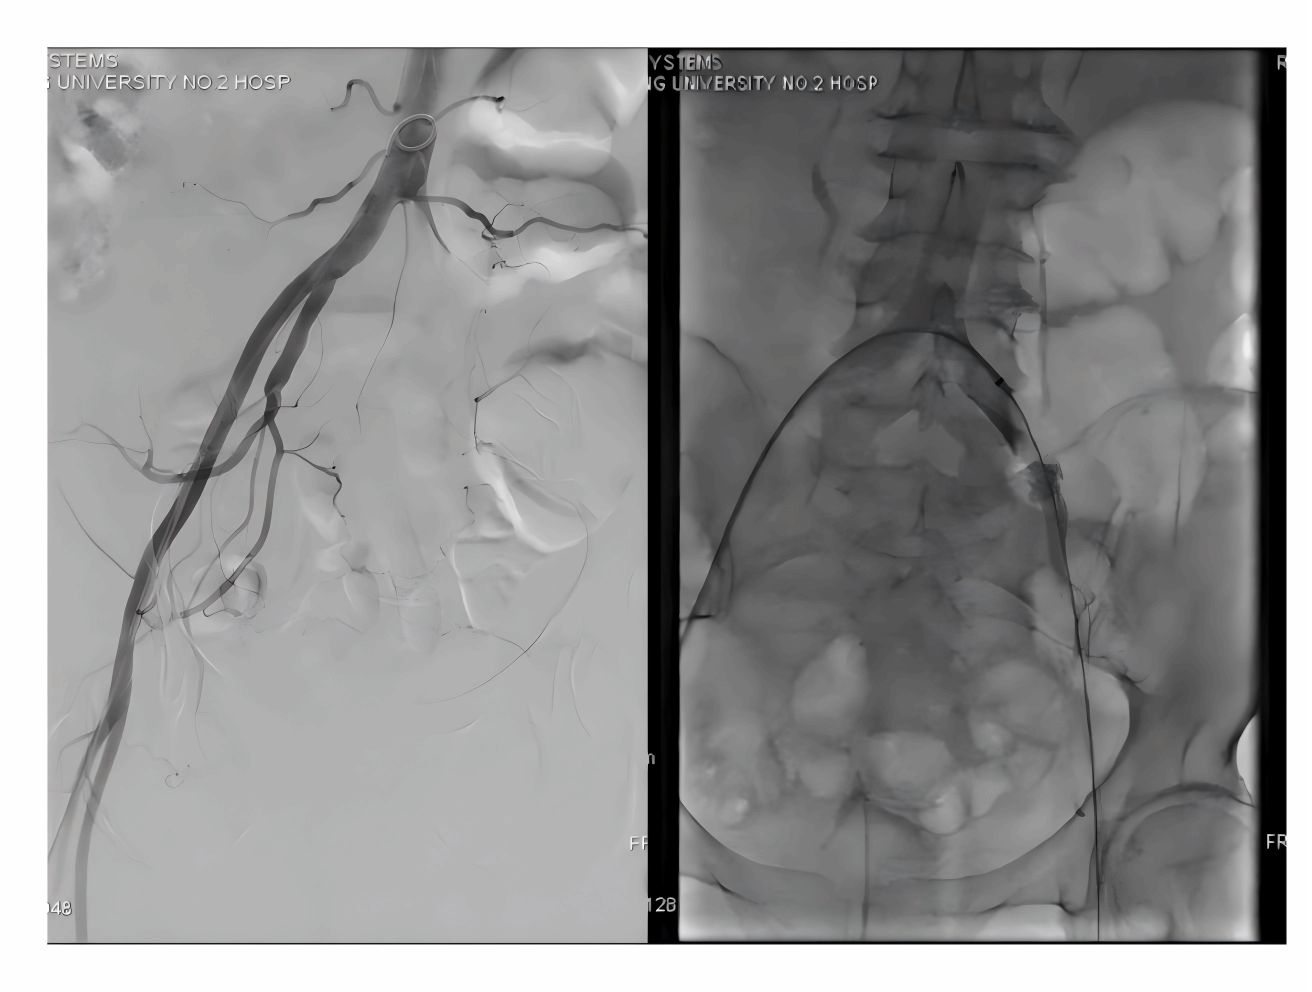

患者术前造影患侧肢体血管完全不显影

开通后的患侧动脉造影